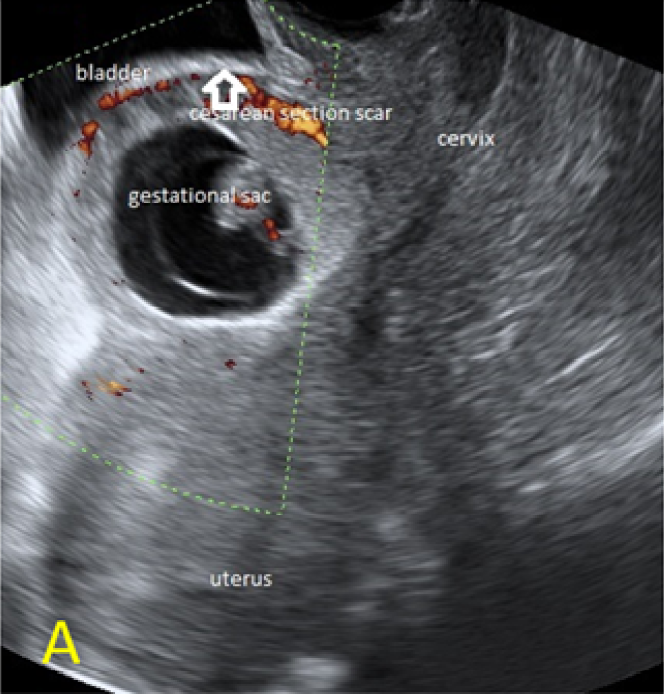

A 22-year-old secundigravida, presented to our Hospital with acute pelvic pain and vaginal bleeding. Her medical history included a 2-year prior caesarean delivery. The patient was in a stable condition and the clinical exam was unremarkable. As the urinary pregnancy test was positive, a transvaginal ultrasound scan was performed to evaluate the pregnancy location and viability. The exam revealed an empty uterine cavity but identified the gestational sac at the level of the caesarean scar with a live embryo (174 beats per minute), measuring 8 weeks and 5 days by crown-rump length. (Figures 1). Because the trophoblastic tissue was noted with an anteriorly location, urinary bladder invasion was suspected based on the ultrasonographic signs: poor identification of the bladder wall, the lack of the sonolucent space and increased vascularization with abnormal pattern (Figure 2). The patient blood tests results were normal, and beta-human chorionic gonadotropin (b-HCG) value was 145.000mUI/ml. After proper counselling and written informed consent the patient opted for a medical conservative treatment with desire to preserve her fertility.

Figure 1. A: the gestational sac is located at the level of the uterine isthmic scar, grey-scale and Power Doppler transvaginal evaluation. B: an embryo with a crown-rump length (CRL) that corresponds to 8 weeks and 1 day is found with normal fetal heart activity (C).